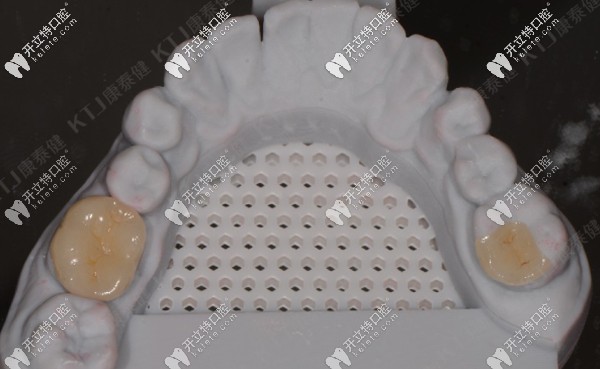

5、打印模型、康泰健嵌體制作

打印模型及康泰健嵌體制作